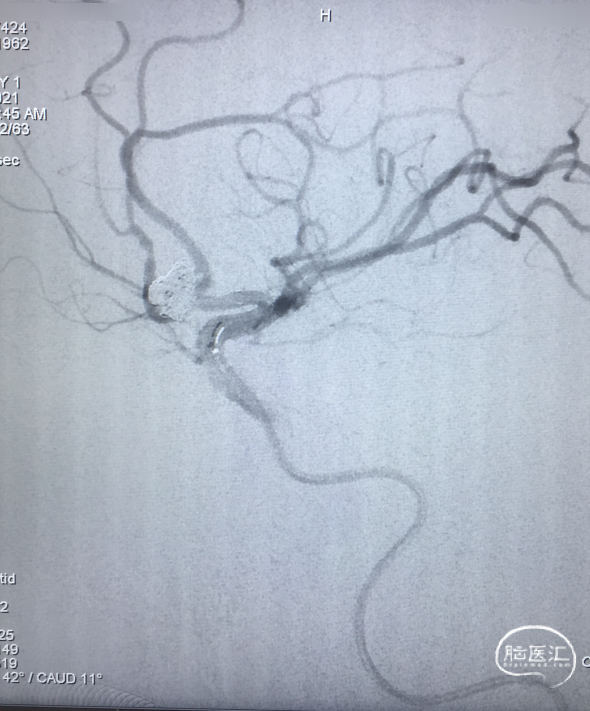

栓塞后即刻影像

工作角度造影显示动脉瘤栓塞致密,LACA A1、ACoA、双A2显影良好,左A2似有血栓(左图)。直头SL-10退至LACA A1末端,推注替罗非班1ml(右图)。

用药后再造影

再造影,发现RACA A2显影差,局部推注替洛非班无效,考虑前交通动脉血流受限,决定支架内球囊扩张。

术后影像

扩张术后造影:显示RACA血流恢复。

术后30分钟造影:LICA正侧位显示良好。

术后支架重建及蒙片:显示支架完全打开,贴壁充分,动脉瘤栓塞致密。